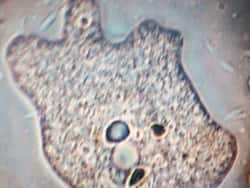

Brain Fever: Karnataka Issues Safety Advisory For Sabarimala Pilgrims Amid Brain-Eating Amoeba Concerns

As thousands of pilgrims prepare to attend Sabarimala Yatra that happens every year between mid-November and mid-January, the Karnataka government in a recent safety advisory urges people to understand the risks, symptoms and precautions of Brain-Eating Amoeba.